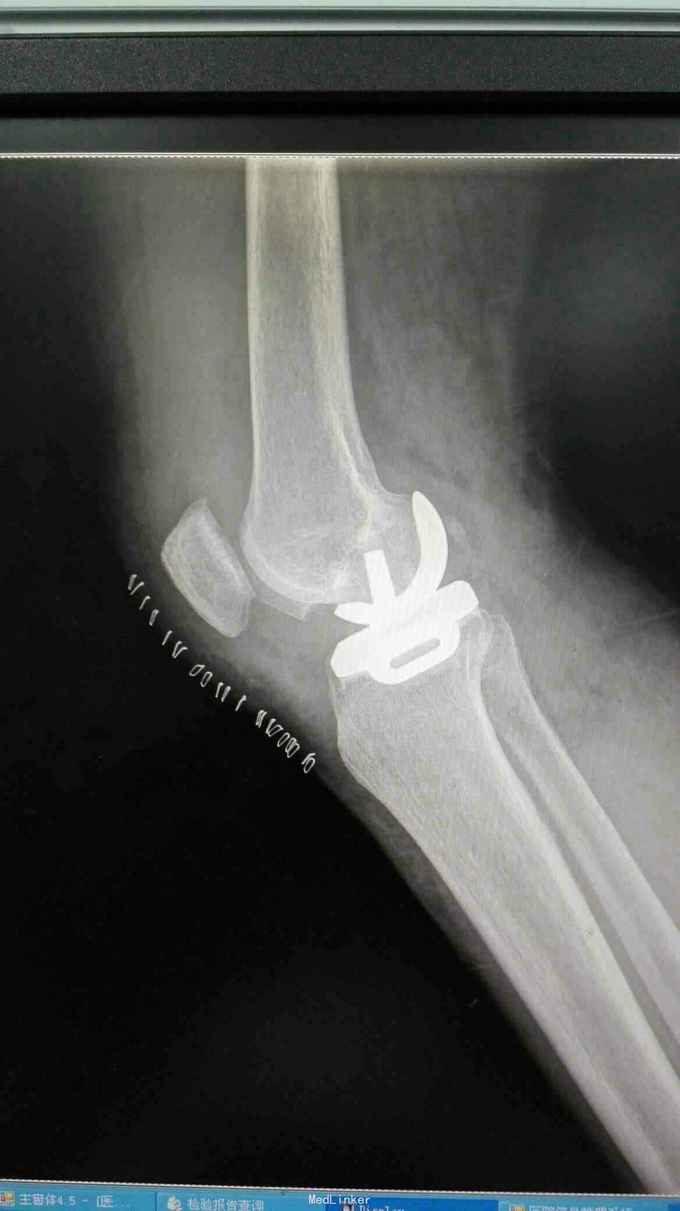

右膝外形正常,皮温正常,右膝内前方压痛(+),前后抽屉试验(-),侧方应力试验(-)、研磨试验内侧(+),关节活动度正常,左膝正常。 站立位膝关节正侧位片提示:右膝关节轻度退行性变,内侧关节间隙稍变窄 右膝关节MRI提示:右股骨内侧髁水肿,考虑局部骨坏死 实验室检查:各炎症指标均正常

诊断:1、右股骨内侧髁骨坏死 2、右膝关节骨性关节炎 治疗:行右膝关节单髁置换术

术后当天下床站立,第二天行走,基本无疼痛,屈伸活动0~120。术后5天出院。 膝关节单髁置换是治疗单侧间室病变有效手段,临床上最常见为膝关节内侧单间室病变,与TKA相比,手术创伤小,恢复快,病人满意度高。行单髁置换满足条件必需是单间室病变,不能太肥胖,韧带完整,可纠正的内外翻畸形及屈曲挛缩小于15度,活动度基本正常。